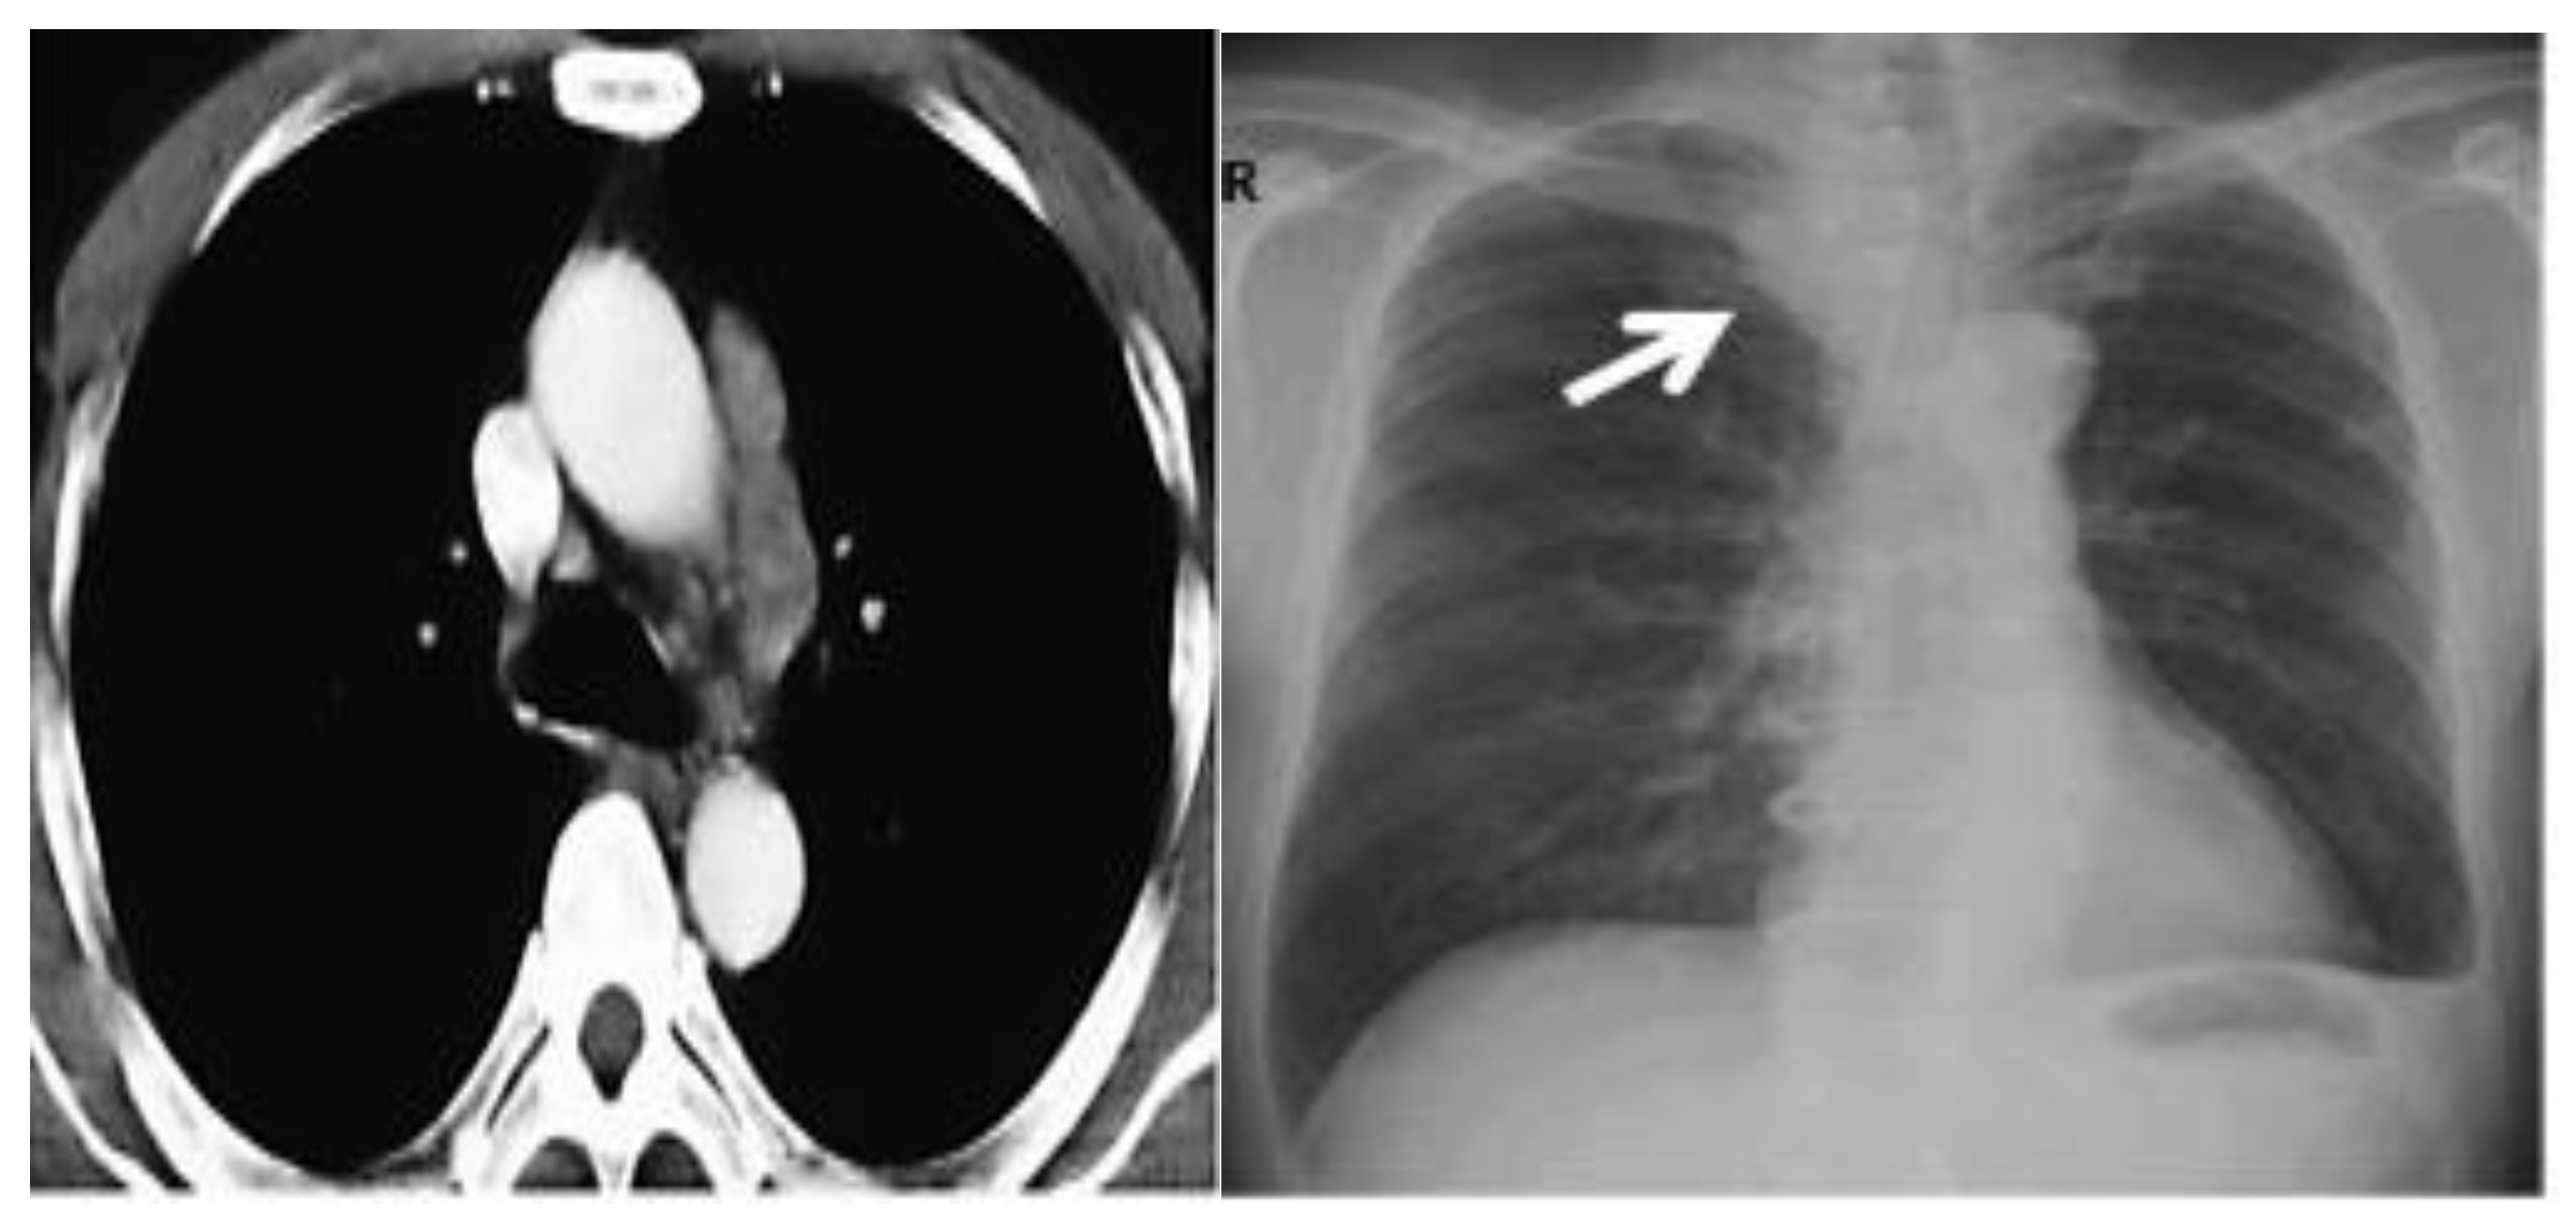

A CT scan and biopsy showed the presence of small cell lung cancer, stage IVA (T4 N3 M1a). The CT scan showed images of a hypermetabolic left pulmonary hilar tumor (Figure 3).

The patient performed a follow-up with PET-CT after 6 months which showed no pleural or pericardial effusion, nor ilio-mediastinal lung tumor and axial or supraclavicular adenopathies. These were only small ilio-mediastinal adenopathies and a slight mediastinal thickening (Figure 8).

Figure 3. CT scan image showing hypermetabolic left pulmonary hilar tumor from male SCC patient.

Figure 8. CT scan image, 6 months after treatment with cryotherapy and immunotherapy of the female patient with SCC.